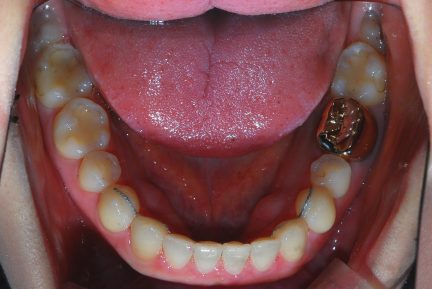

État initial

- Arcades alignées et coordonnées

- Arcades harmonieuses obtenues

Surtout après la fermeture d'espace, le contrôle de l'inclinaison linguale buccale des dents antérieures inférieures était excellent.